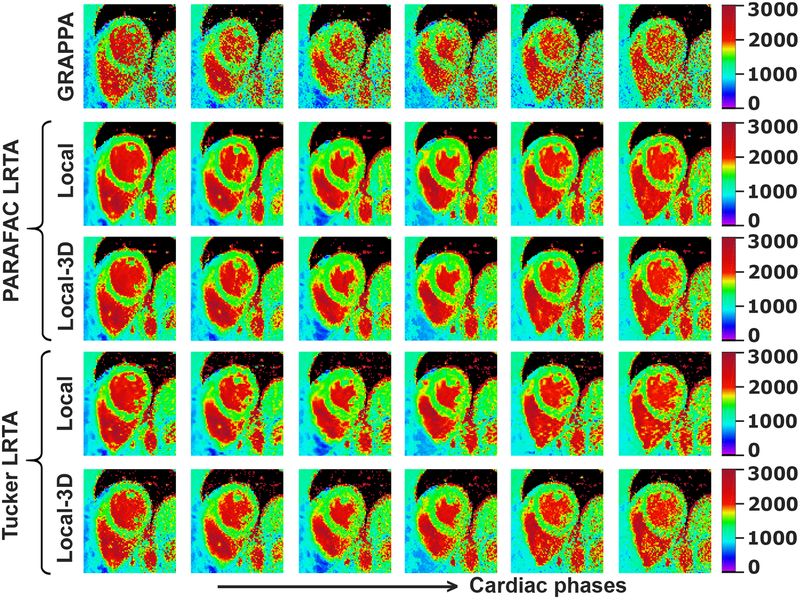

Figure 5 depicts representative dynamic quantitative T1 maps for the same subject using local LRTA approaches. As in global LRTA approaches, all local LRTA methods achieved T1 times that were in good agreement with baseline low-resolution images. These local LRTA techniques further suppressed the residual artifacts in global LRTA approaches and improved the quality of the T1 maps compared to their global LRTA counterparts. The local LRTA improvements over GRAPPA and global LRTA methods were also observed quantitatively. The precision values were 122±20 ms and 127±19 ms for local and local-3D PARAFAC LRTA and were 147±23 ms and 179±27 ms for local and local-3D Tucker LRTA approaches, respectively.

Fig. 5:

Dynamic quantitative T1 maps for the same subject in Figure 4, reconstructed using GRAPPA, and the local PARAFAC and Tucker LRTA processing approaches. T1 maps of six cardiac phases equally spaced across the R-R interval are shown. For both PARAFAC and Tucker decompositions, local LRTA methods significantly mitigate noise amplification, while eliminating residual artifacts that affect the inferior segment, especially in end diastolic phases, when using the global LRTA approaches. Overall precision of the myocardial T1 values for this subject across all cardiac phases were 122±20 ms and 127±19 ms for local and local-3D PARAFAC LRTA and were 147±23 ms and 179±27 ms for local and local-3D Tucker LRTA approaches, respectively..